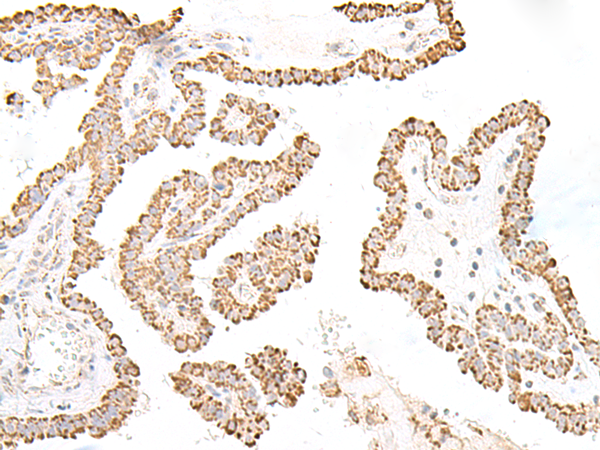

ELISA, IHC |

IHC positive control: |

Human esophagus cancer and Human thyroid cancer |

IHC Recommend dilution: |

50-300 |